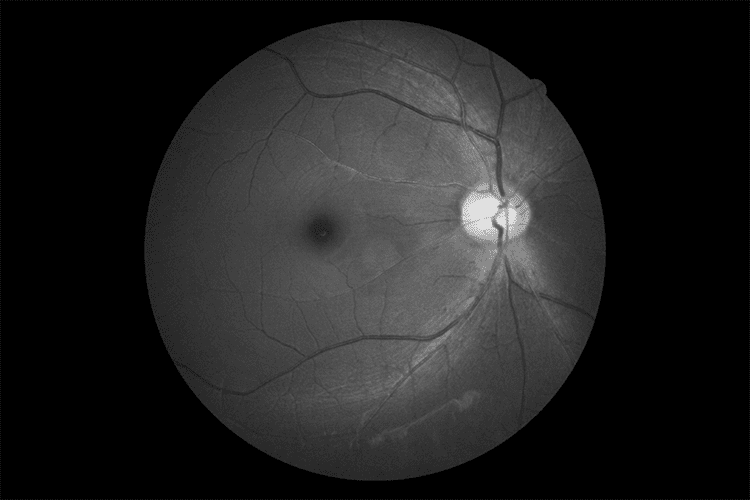

Технологія Canon Opacity Suppression

Цей унікальний і складний програмний інструмент відновлює початкову яскравість і колір сітківки. Технологія зменшує несприятливий вплив помутнінь очей, таких як катаракта, для більш чіткого перегляду кровоносних судин, що призводить до того, що незрозумілі структури стають більш впізнаваними.